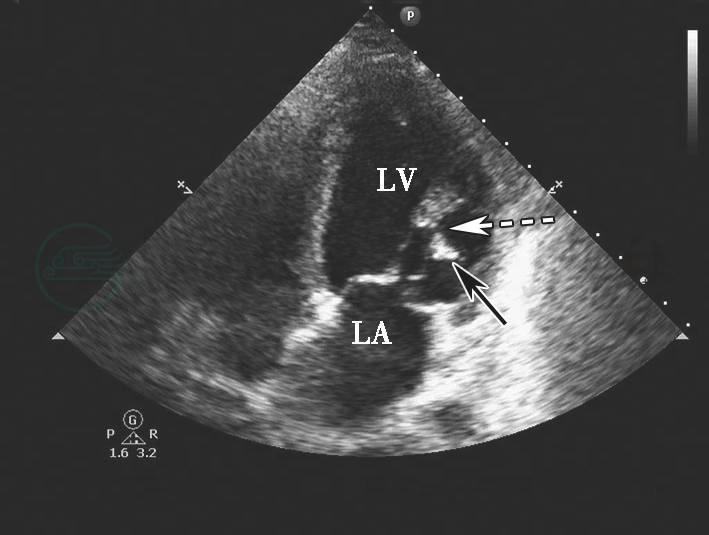

图4心肌梗死乳头肌断裂二维切面图像

心尖四腔心切面显示二尖瓣前外乳头肌部分断裂(虚箭头示)及乳头肌断端(实箭头示)。LA.左心房;LV.左心室。